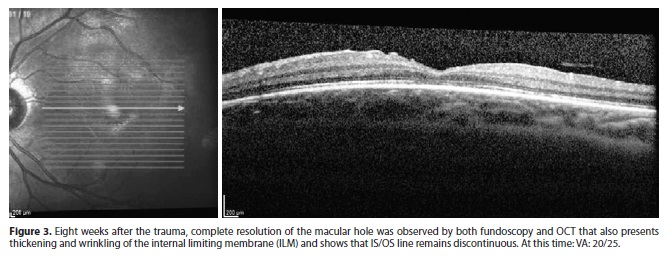

Eight weeks after the first exam, the best-corrected visual acuity improved from 20/100 to 20/25. Complete resolution of the macular hole was observed, as determined by both fundoscopy and OCT imaging. At this time, the OCT (Figure 3) showed a complete resolution of the full-thickness macular hole, there was no area of hyporeflectivity beneath the ELM, but the IS/OS line remained discontinuous. Thickening and wrinkling of the internal limiting membrane (ILM) werealso observed.

It is remarkable to observe that, at 8 weeks in the follow-up, despite VA improvement, the SD-OCT showed anatomic abnormalities, as thickening and wrinkling of the ILM, and discontinuity of the IS/OS line.